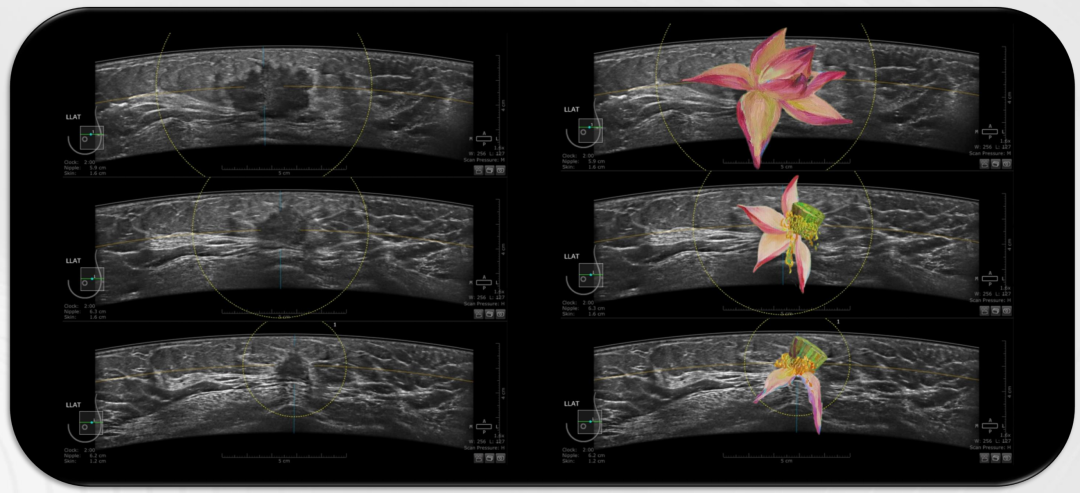

宋宏萍 肖瑤 空軍軍醫大學西京醫院

《腫瘤的消退 — “殘荷”》

自動乳腺超聲ABUS成像,標準化圖像直觀、形象地展示了乳腺癌新輔助治療不同週期腫瘤特徵變化,栩栩如生,酷似夏日裏一朵凋零的“荷花”,從亭亭玉立到枝零飄落 。